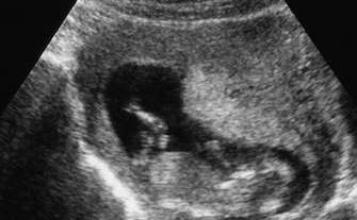

C’est une première en France. Les équipes de l’hôpital Trousseau et de l’hôpital Necker ont opéré un fœtus des mois avant sa naissance. L’intervention s’est déroulée en juillet, au cinquième mois de la grossesse de la mère. Au cours d’une conférence de presse, les médecins de l’Assistance Publique-Hôpitaux de Paris (AP-HP) ont annoncé avec soulagement l’heureuse nouvelle : le bébé est né, il va bien, et sa mère aussi.

L’intervention a duré deux heures. Elle avait pour objectif de corriger une malformation congénitale, le spina bifida. Cette maladie correspond à un développement incomplet de la colonne vertébrale lors de la formation du fœtus. Elle empêche les vertèbres lombaires de se fermer, laissant la moelle épinière et ses racines nerveuses sans protection. A cause d’une fuite du liquide céphalo-rachidien, le cervelet s’affaisse au cours de la grossesse. Cause de paralysie et d’incontinence, c’est la maladie la plus fréquente du système nerveux central, même si elle reste assez rare – 1 grossesse sur 1000 environ, soit 800 cas chaque année.

L’opération, inédite en France, est extrêmement délicate. Pour accéder au fœtus, les chirurgiens doivent extérioriser l’utérus et l’inciser sur quelques centimètres. « L’utérus doit être mou comme une chaussette, précise le gynéco-obstétricien Jean-Marie Jouannic, qui a dirigé la manœuvre. On administre à la mère des médicaments contre les contractions et des drogues anesthésiques qui agissent également sur le fœtus ».

Les médecins accèdent ainsi au dos du fœtus qui porte la malformation. Vient alors le temps neurochirurgical. « Le chirurgien recouvre la moelle épinière en soudant l’enveloppe qui normalement la recouvre. Puis il suture la peau du fœtus », explique Jean-Marie Jouannic.